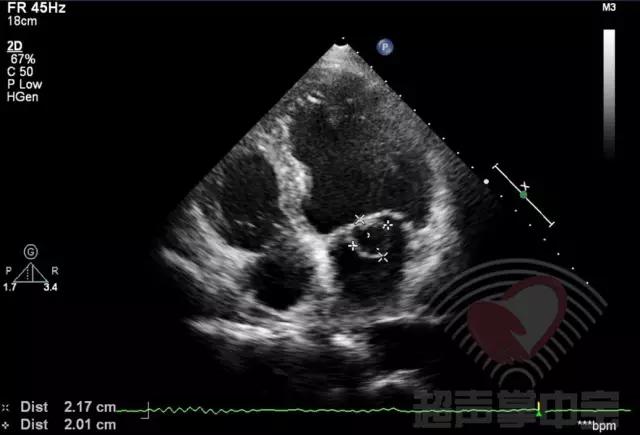

二尖瓣充血性囊肿,二尖瓣血性囊肿是什么意思 图1:心尖四腔心切面显示二尖瓣前叶增厚,前叶左房面可见一囊袋状物附着,大小2.01×2.17cm,囊壁完整,其内透声良好